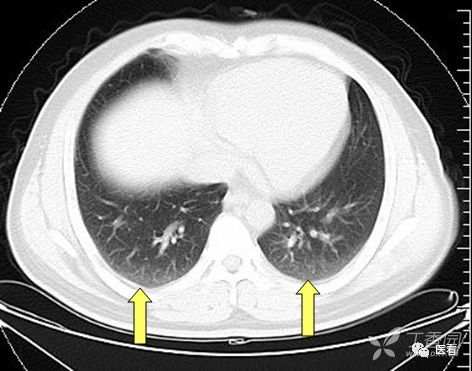

肺坠积效应

由于血液因引力作用向近地侧沉积,因此两肺下叶背侧胸膜下带血液相对较多,双肺后部肺野密度增高(箭示),称之为坠积效应。在老年人及长期卧床者尤其明显。如果不认识可能误认 为肺内炎症或肺间质纤维化。